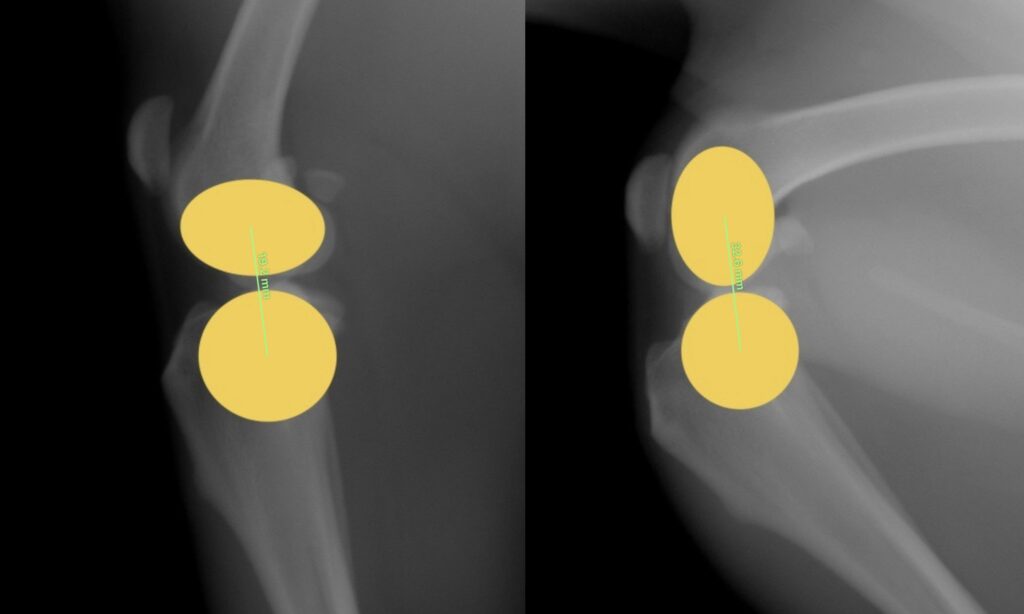

曲げ伸ばしで起こる関節の変化に図形を当てはめてみましょう。

上図のように。実際の膝関節は、円と円の構造というよりは、楕円と円の構造になっています。楕円の長軸と単軸の半径の違いによって、曲げ伸ばしの際の中心点間の距離が変わります。このため、前述した、『膝を曲げた状態に合わせて人工繊維を設置すると膝を伸ばした時には緩くなり、膝を伸ばした状態に合わせて設置すれば膝を曲げた時に人工繊維に過剰な力がかかってしまう』という問題が発生してしまい、これがECRの欠点となってしまっていました。

上図のように、膝関節を円と円に例えることができると、膝を曲げても伸ばしても中心点を結んだ線の距離が変わらないイメージは伝わりやすいかと思います。